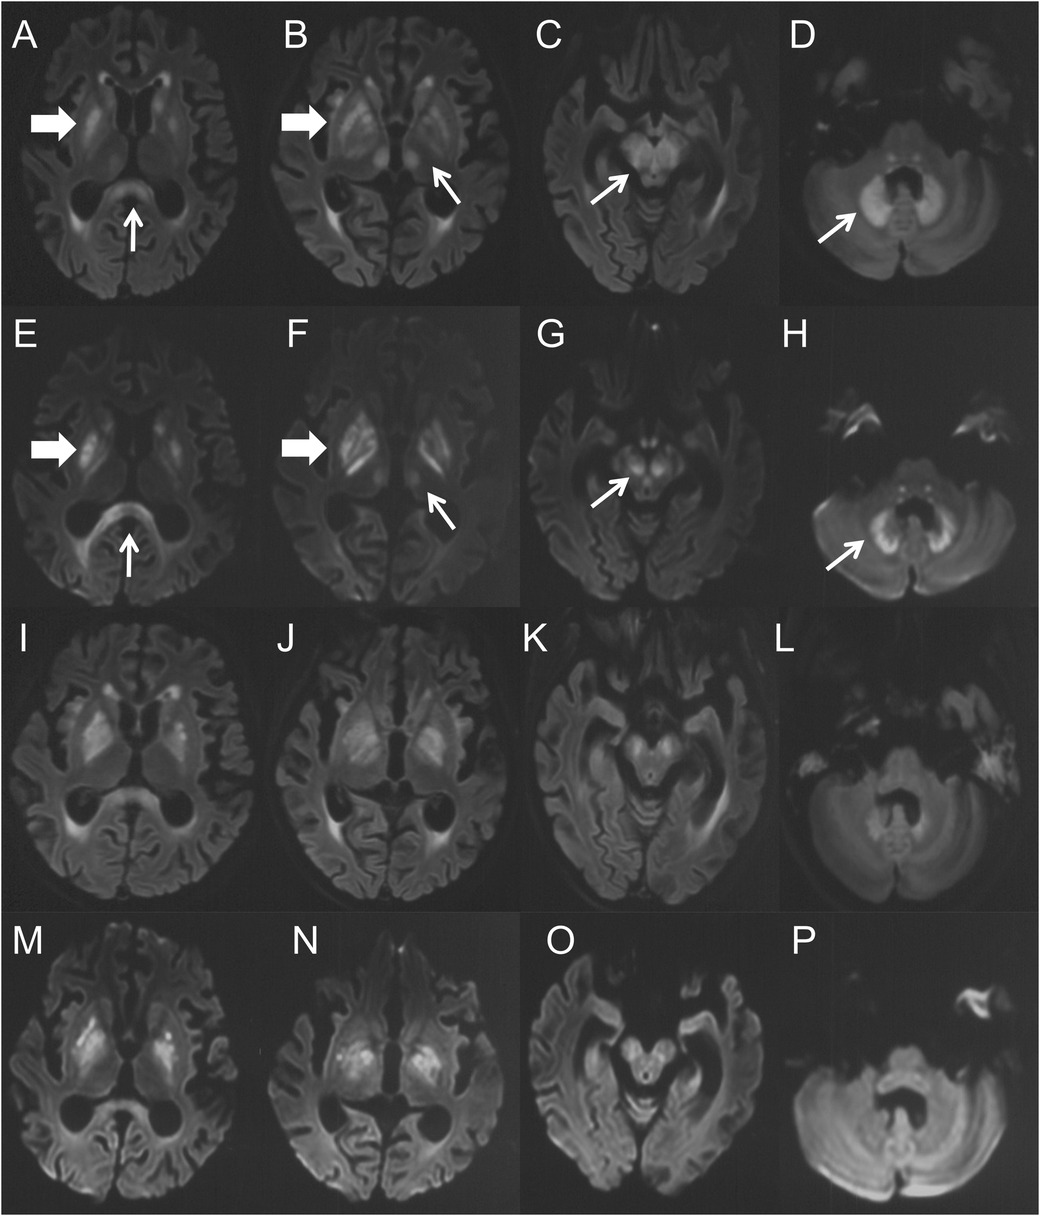

Ten days after the neurological symptom onset, she was transferred to our hospital. Based on typical clinical manifestations and characteristic brain MRI lesions, MIE was diagnosed. Metronidazole was immediately discontinued, and vitamin B1 supplementation was initiated. At this point, metronidazole had been administered for 58 days, with a cumulative dose of 46.4 g. Two days after discontinuation, a repeat brain MRI showed the lesions became more diffuse in the regions of basal ganglia, inferior colliculus of quadrigeminal bodies, midbrain, pons, thalamus and paraventricular white matter, in addition to splenium of corpus callosum and dentate nucleus (Figures 2A–H). Clinical improvement emerged four days after discontinuation with heightened alertness and responsiveness to simple verbal commands. A follow-up brain MRI 10 days later showed partial resolution of lesions (Figures 2I–P). Eleven days after discontinuation, the patient's ocular movements returned to normal, but extrapyramidal symptoms persisted. Regrettably, approximately one month after metronidazole withdrawal, the patient succumbed to acute gastrointestinal hemorrhage secondary to graft-vs.-host disease (GVHD) (Figure 3).

Figure 2. (A–H) were the brain MRI performed 14 days after the onset of MIE. (A–D) were the axial FLAIR images, (E–H) were the DWI images. Symmetric hyperintensity lesions presented over the splenium of corpus callosum (A,E, thin arrows), basal ganglia (A,B,E,F, thick arrows), thalamus (B,F, thin arrows), midbrain (C,G, thin arrows) and dentate nucleus (D,H, thin arrows). (I–P) were the brain MRI performed 22 days (10 days after drug withdrawal) after the onset of MIE. (I–L) were the axial FLAIR images, and (M–P) were the DWI images. They demonstrated complete (thalamus) or partial resolution (others) of the lesions.

Neuroimaging plays a pivotal role in diagnosing MIE. Characteristic brain MRI lesions include symmetrical T2W/FLAIR hyperintensities. These lesions mainly involve the dentate nuclei of the cerebellum, midbrain, and splenium of the corpus callosum, and also involve the dorsal pons, medulla oblongata, basal ganglia, thalamus, cerebellar white matter, and cerebral white matter (25). Restricted diffusion is frequently present within these lesions, but the ADC values are variable, exhibiting low, normal, or high signals. Typically, ADC signals in lesions of the corpus callosum and cerebral white matter are low while those are uncertain in dentate nuclei and other regions. This difference in ADC signal suggests that metronidazole neurotoxicity may involve both cytotoxic and vasogenic edema mechanisms. Our patient had the characteristic MRI changes, and there was significant radiological improvement after metronidazole withdrawal (Figure 2).

The treatment of MIE lies in the timely discontinuation of metronidazole. Given that metronidazole may serve as a thiamine antagonist and interfere with its metabolism, routine thiamine supplementation has been suggested as adjunctive therapy. Most cases of MIE are reversible, with clinical and imaging improvements after metronidazole withdrawal, but a few cases may leave neurological sequelae (27). In this patient, metronidazole was immediately discontinued and vitamin B1 was added after considering MIE. Her encephalopathic manifestations gradually improved 4 days after cessation. Follow-up brain MRI at 10 days after drug withdrawal demonstrated partial resolution of signal abnormalities, while extrapyramidal symptoms persisted. Due to the delayed diagnosis, the neurological involvement in the patient has become more extensive, and the extrapyramidal symptoms failed to resolve after drug withdrawal. Regrettably, approximately one month after metronidazole withdrawal, the patient succumbed to acute gastrointestinal hemorrhage secondary to GVHD.